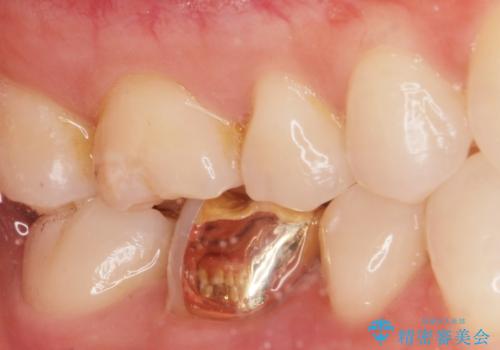

劣化した保険の詰め物部分の治療をしたい。

- 過去の樹脂の治療の劣化を治したいとの事で来院。大臼歯の歯は樹脂の範囲が大きくセラミックインレーで処置しても割れてしまう可能性があるため被せ物のご案内をしたところ、なるべく歯を削りたくないとのことでPGAアンレー(ゴールドアンレー)での治療となりました。手前の歯はセラミックの詰め物で治療する事ができました。

歯質の削除量をなるべく最小限にして治療が終わりました。

セラミック、ゴールド共に適合が良く虫歯の再発のリスクが低くなります。